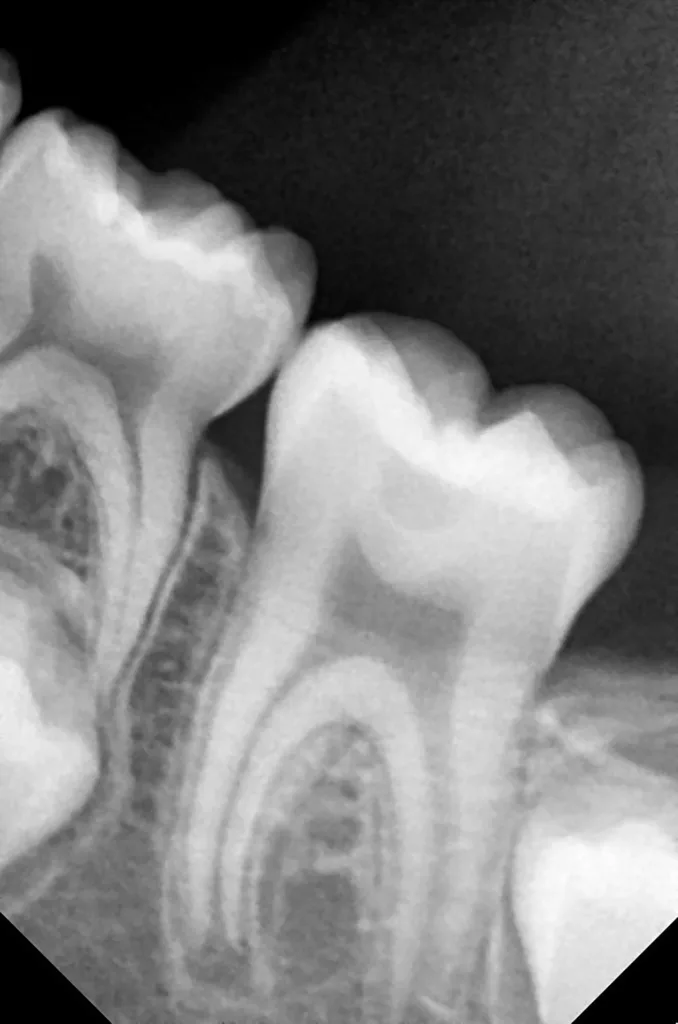

In der Folgezeit kam die Patientin mindestens einmal pro Jahr zur klinischen und radiologischen Untersuchung. Die Eltern wurden darauf aufmerksam gemacht, dass bei einer bakteriellen Penetration in die PEIR-Defekte diese komplett restaurativ versorgt werden sollten, spätestens jedoch bei kompletter Ausbildung der Zahnwurzeln. Während der ersten drei Jahre erweis sich der Befund klinisch stabil (Abb. 4 und 5). Die PEIR-Defekte sind bezüglich Größe und Form unverändert geblieben, und die Entwicklung der Wurzeln verlief physiologisch (Abb. 6 und 7). Auch nach 7 Jahren der Beobachtung blieb die Situation der Unterkiefermolaren sowohl aus klinischer als auch radiologischer Sicht immer noch stabil (Abb. 8 bis 11). Die Wurzeln der ersten Backenzähne sind vollständig ausgebildet (Abb. 10 und 11), die Grenze des PEIR-Defektes bei Zahn 46 ist deutlicher geworden, das Dentin zwischen Defekt und Pulpa erscheint dicker (Abb. 11). Ungeachtet der Tatsache, dass die PEIR-Defekte beim inzwischen zwölfjährigen Kind ohne Risiko und deutlich leichter restauriert werden könnten und das Risiko einer Infizierung nach wie vor bestand, wollten die Eltern die Situation weiter beobachten und eine erneute Behandlung zunächst noch aufschieben. Obwohl auf dem Röntgenbild des Zahnes 16 keine Entwicklung des PEIR-Defektes (Grad 2 der Läsion nach Seow) zu beobachten war (Abb. 12) und der Zahn die ganzen sieben Jahren beschwerdefrei blieb, sah die Krone klinisch dunkler aus (Abb. 13). Das war ein Hinweis auf eine bakterielle Penetration mit einer manifesten Kariesentwicklung. Somit war es erforderlich, den PEIR-Defekt des Zahnes 16 zu öffnen und mit einer Kompositrestauration zu versorgen.

Im Rahmen der jährlichen Kontrolluntersuchung wurde bei einem achtjährigen Mädchen auf der routinemäßig angefertigten Röntgenaufnahme eine mittelgroße PEIR des Zahnes 46 (Grad 2 der Läsion nach Seow) entdeckt (Abb. 43). Die Patientin war komplett beschwerdefrei und der Zahnschmelz des betroffenen Zahnes sah intakt aus (Abb. 44 und 45). Weil auch hier der PEIR-Defekt gräulich durchschimmerte (Abb. 44 und 45) und der Zahn bereits seit einem Jahr durchgebrochen war, entschieden wir uns in diesem Fall, den Defekt klassisch mit Komposit zu restaurieren. Unter Lokalanästhesie mit Septanest 1/100 000 (Septodont, Frankreich) wurde zunächst Kofferdam mithilfe der Klammer U67 (KSK Dentech, Japan) gelegt (Abb. 45). Weder visuell noch mittels Sondierung konnte eine Verbindung zur Läsion festgestellt werden. Deswegen wurde an der Stelle, an welcher der PEIR-Defekt gräulich schimmerte, intakter Zahnschmelz der lingualen Querfissur entfernt (Abb. 46). Innerhalb der Läsion wurde nekrotisches intrakoronales Weichgewebe vorgefunden (Abb. 47), das problemlos mittels RONDOflex plus 360 (KaVo Dental, Deutschland) mit dem 27-µm-Pulver vollständig entfernt werden konnte. Der Boden des Defektes zeigte eine glatte, runde Form sowie helles, hartes und intaktes Dentin. Eine Präparation war nicht erforderlich, es wurde lediglich die Zahnschmelzkante geglättet (Abb. 48). Für die Restauration kamen erneut das Adhäsiv Optibond FL (Kerr, USA) und das Komposit Estelite ASTERIA OCE, A2B und Universal Flow AO2 (Tokuyama, Japan) zur Anwendung (Abb. 49). 6 Monate nach der Behandlung zeigte sich das Ergebnis sowohl aus klinischer als auch radiologischer Sicht stabil wie die Abbildungen 50 und 51 zeigen.